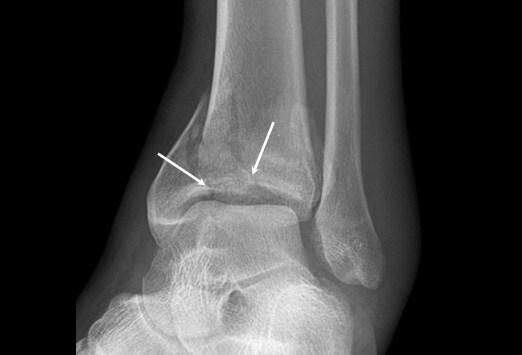

En medicina, se denomina fractura de Gosselin a un tipo especial de fractura ósea que afecta a la región distal de la tibia, cerca del tobillo. Se caracteriza por una rotura en forma de V en la región distal de la tibia que origina dos fragmentos óseos, uno anterior y otro posterior. Debe su nombre al cirujano francés Leon Athanese Gosselin (1815-1887) que realizó la primera descripción.[1][2][3] La fractura de Gosselin es un subtipo de las fracturas de pilón tibial, fracturas de la tibia que afectan a su metáfisis y epifisis inferior compremetiendo la articulación del tobillo.[4]